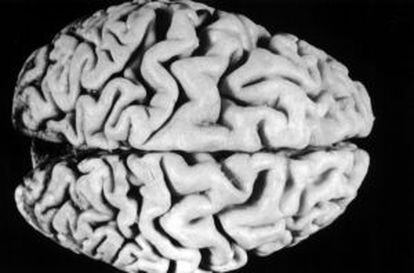

Los componentes están ahí, pero el cóctel no tiene por qué producirse. Es la conclusión de un trabajo básico (no por lo sencillo, sino porque le falta un largo recorrido para un posible uso clínico) que publica Neuron y que explica la causa última por la que unas personas tienen alzhéimer y otras, no. La razón fisiológica lleva a lo que ya se sabe: la acumulación de unas proteínas, las llamadas beta-amiloides, en el cerebro que llevan a una pérdida de funcionalidad de las neuronas. Pero estas proteínas no vienen de la nada. Como en todos los procesos biológicos, son el resultado de una larga cadena de procesos, y ahí está la clave.

En concreto, los investigadores de la Universidad de California en San Diego han estudiado el paso previo a la aparición de las beta-amiloides, y esto les ha llevado a otras dos proteínas. Una, su origen natural, las llamadas proteínas precursoras del amiloide (APP) –un nombre bastante obvio, como puede verse-; la otra, la enzima (otro tipo de proteína) que la transforma, la llamada beta-secretasa (BASE).

La conclusión de los investigadores es que todos tenemos abundantes copias de ambas. Pero lo que hace que unas personas desarrollen alzhéimer y otras no es su capacidad para mantenerlas separadas. Se trata de un sistema de regulación bastante extraño en la bioquímica, ya que no obedece a moléculas protectoras o algo similar, sino a simple cercanía física. Como dice el investigador Subhojit Roy, es como tener la dinamita y la cerilla: se trata de que no se toquen.